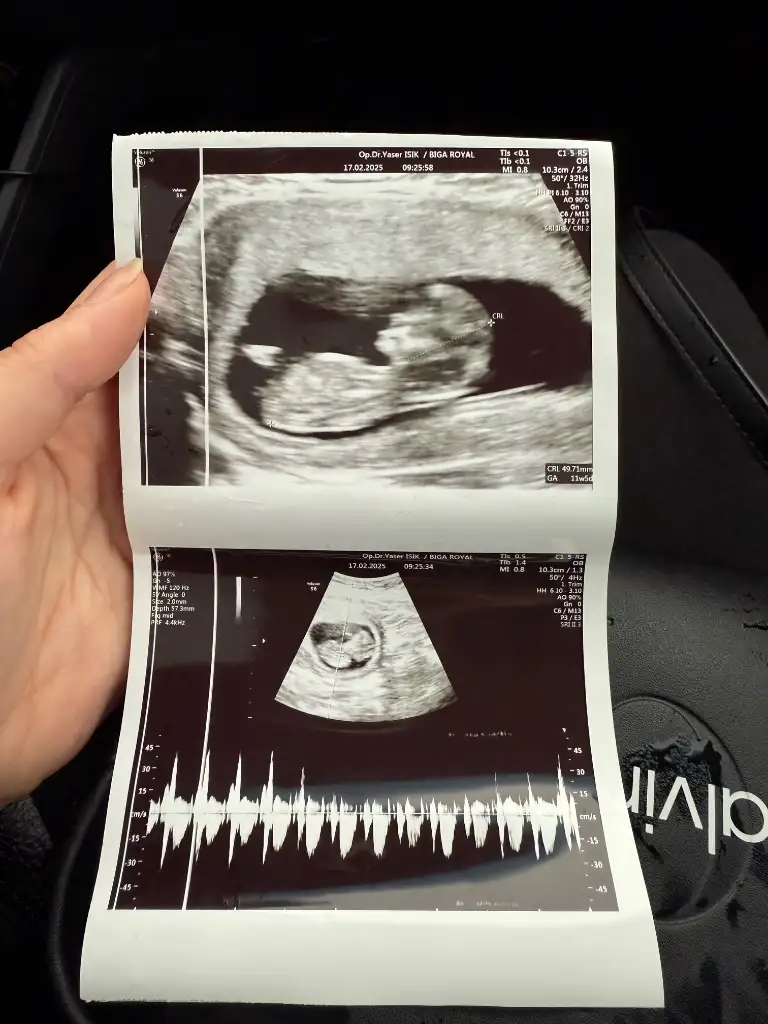

6 haftalık benimkinide yorumlar mısınız lütfenKız bence seninki de

Biliyorum çok küçük ama benimkinide yorumlar mısınız karından ultrasonKız bence seninki de

Erkek hissettimKızlar 10 haftalık hamileyim cinsiyet tahmini sizce nedir

Bunada bakar mısınızKese yuvarlak kız gibi

Başka foto var mı iki bacak arası gibi bu ama bulanık çıkmış gördüğüm çıkıntıysa erkek ama emin olamadımBunada bakar mısınız

Bunlar var canimBaşka foto var mı iki bacak arası gibi bu ama bulanık çıkmış gördüğüm çıkıntıysa erkek ama emin olamadım

Bunada bakar mısınız 11

KızBunada bakar mısınız 11

Başka foto var mı iki bacak arası gibi bu ama bulanık çıkmış gördüğüm çıkıntıysa erkek ama emin olamadım

Kızlar tahmininiz nedir

Fotolar doktor taarafından hiç güzel çekilmmemişKızlar tahmininiz nedir

Ama kalp atış hızı erkeki gösteriyor keseyi tam çözemedim şekli beli olmamış fasulye olursa erkek yuvarlak olursü kız olur genelde

Canım buda kese tam yuvarlak değil gibi erkek hissettim kaç haftalıksın küçük gibi iki hafta geçse sanki daha iyi tahmin yapılıır sendedeEki Görüntüle 3551356 Eki Görüntüle 3551357 benimkinede bakabilir misin canım